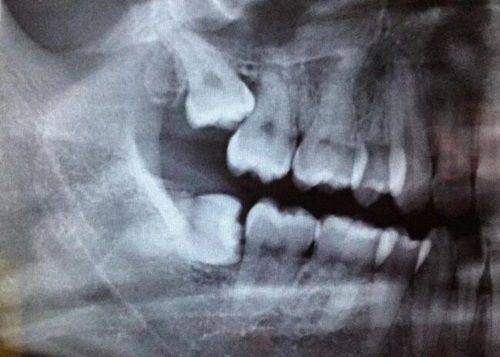

精良诊疗设备

门诊部配备了精良的口腔诊疗设备,部分设备从国外引进。这些当下精良的医疗设备设施,为正确诊断和效率高治疗提供了有力保护。精良的设备能够更精细地检测出患者的口腔问题,从而制定出更合适的治疗方案。